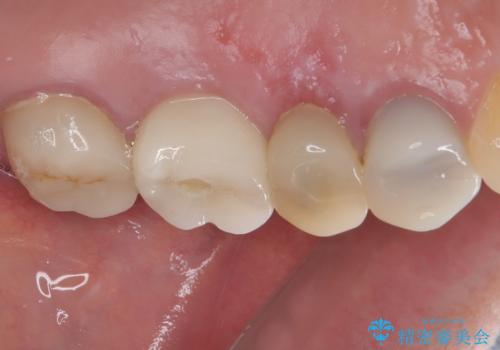

垂直方向への炎症が大きく、抜歯即時埋入はできたものの、即時荷重(インプラント埋入時の仮歯の装着)を可能とする安定値は得られませんでした。

それにもかかわらず、僅か4ヶ月で治療を終えることができ、以前の上顎洞底の挙上を行っていた頃よりも半年以上短縮することができました。